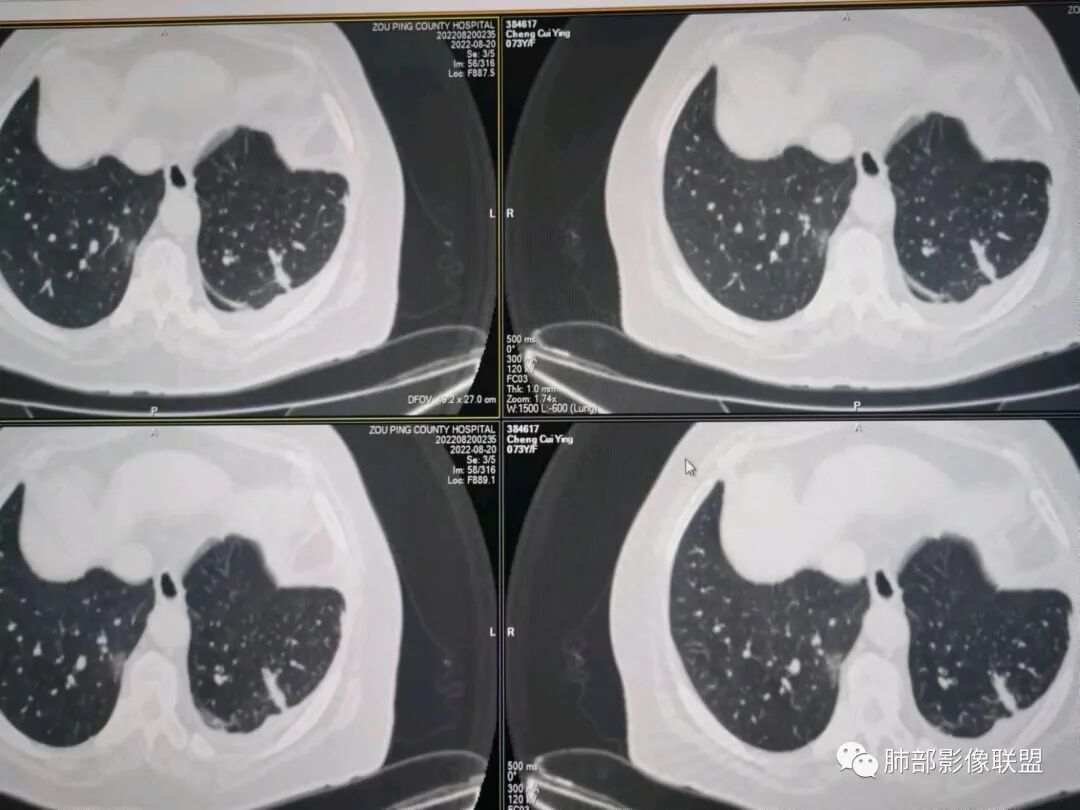

AAA张春雨:左肺胸膜下大小不等的多发病灶,内有支气管半进入征,强化内部不均,患者有明显肺气肿背景,胸阔呈桶状,少量胸腔积液,综合考虑隐球菌感染的可能性最大,鉴别腺癌。

songml:老年女性,反复咳嗽咳痰胸闷4年,加重伴发热一周。左肺下叶后基底段胸膜下肿块影,密度较均匀,边缘较清,侵及胸膜下脂肪间隙。考虑恶性病变,腺癌可能,鉴别真菌感染。

仲夏:老年女性,咳嗽咳痰近4年,左肺下叶胸膜下类圆形肿块,内侧绳索征,内部密度不均匀,可见坏死,周围小空泡,小叶间隔增厚,胸膜下积液,轻度强化,NSE、细胞角蛋白酶19片段高,考虑恶性肿瘤,腺癌?